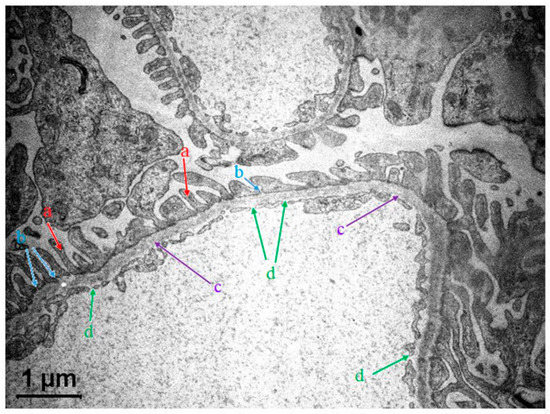

3.2. The Glomerular Filtration Barrier (GFB) in Kidneys

3.2.1. GFB Structure in a Nutshell